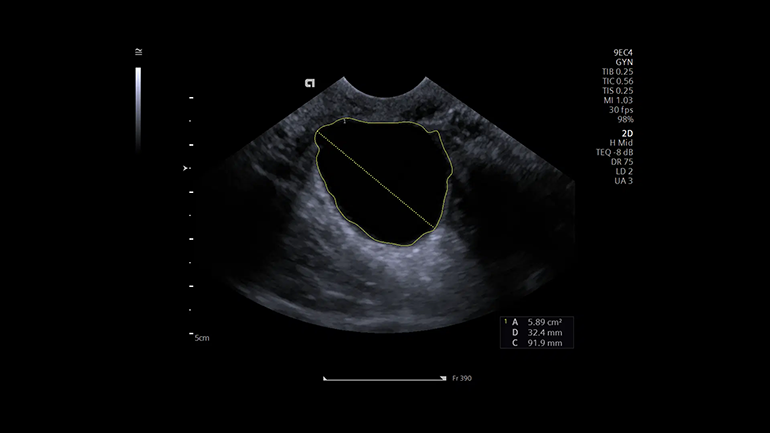

Технология автоматизации процесса измерений в 2D-, M- и допплеровских режимах eSie Measure. Технология eSie Measure позволяет выполнять количественные измерения одним нажатием кнопки, тем самым сокращается количество ручных действий врача-диагноста и повышается воспроизводимость результатов.

Технология автоматизации процесса измерений в 2D-, M- и допплеровских режимах eSie Measure. Технология eSie Measure позволяет выполнять количественные измерения одним нажатием кнопки, тем самым сокращается количество ручных действий врача-диагноста и повышается воспроизводимость результатов. Технология автоматических перинатальных измерений eSie OB. eSie OB автоматизирует выполнение биометрических измерений при акушерских исследованиях. Она не только уменьшает время сканирования и сокращает количество нажатий клавиш, но и повышает воспроизводимость УЗ- исследований.